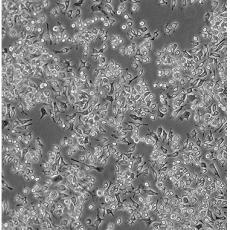

產品名稱 RAW 264.7

中文名稱 小鼠單核巨噬細胞白血病細胞

組織來源 單核巨噬細胞白血病;雄性;BALB/c

細胞種屬 mus musculus, mouse

生長特性 adherent

培養基 DMEM+10% FBS+1% P/S

形態特征 monocyte/macrophage

傳代方法 1:3-1:6

細胞描述 This cell line is easy to propagate, high efficiency for DNA transfection, sensitivity to RNA interference, and supports replication of murine noroviruses. This cell line is negative for surface immunoglobulin(sIg-), Ia(Ia-) and Thy-1.2(Thy-1.2). When this line was established, it was described as not secreting detectable virus particles and negative using the XC plaque formation assay. Based on a published study by Dr. Janet W. Hartley in 2008, this line was demonstrated to express ecotropic and polytropic MuLV, and is positive using the XC plaque assay for virus replication.Ref